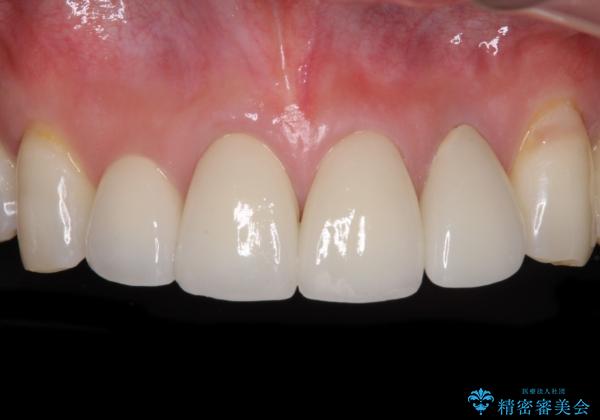

目立つ範囲である前歯4歯をオールセラミッククラウンにて補綴することとしました。

口元の印象が明るくなり、人前で気にせずに笑えるようになりました。